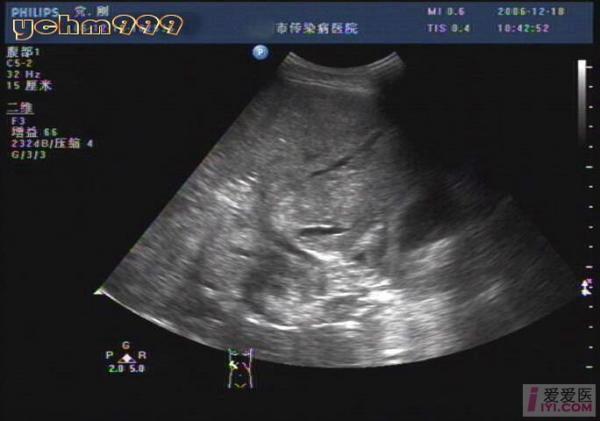

老爸前段时间查出来有酒精肝 今天刚刚复查了 有医生在吗?

脂肪肝,酒精肝 肝回声增粗说明肝脏有了损伤,脂肪浸润等问题,常见的

不像脂肪肝,像酒精性肝病

酒精性肝硬化伴肝ca,门脉血栓